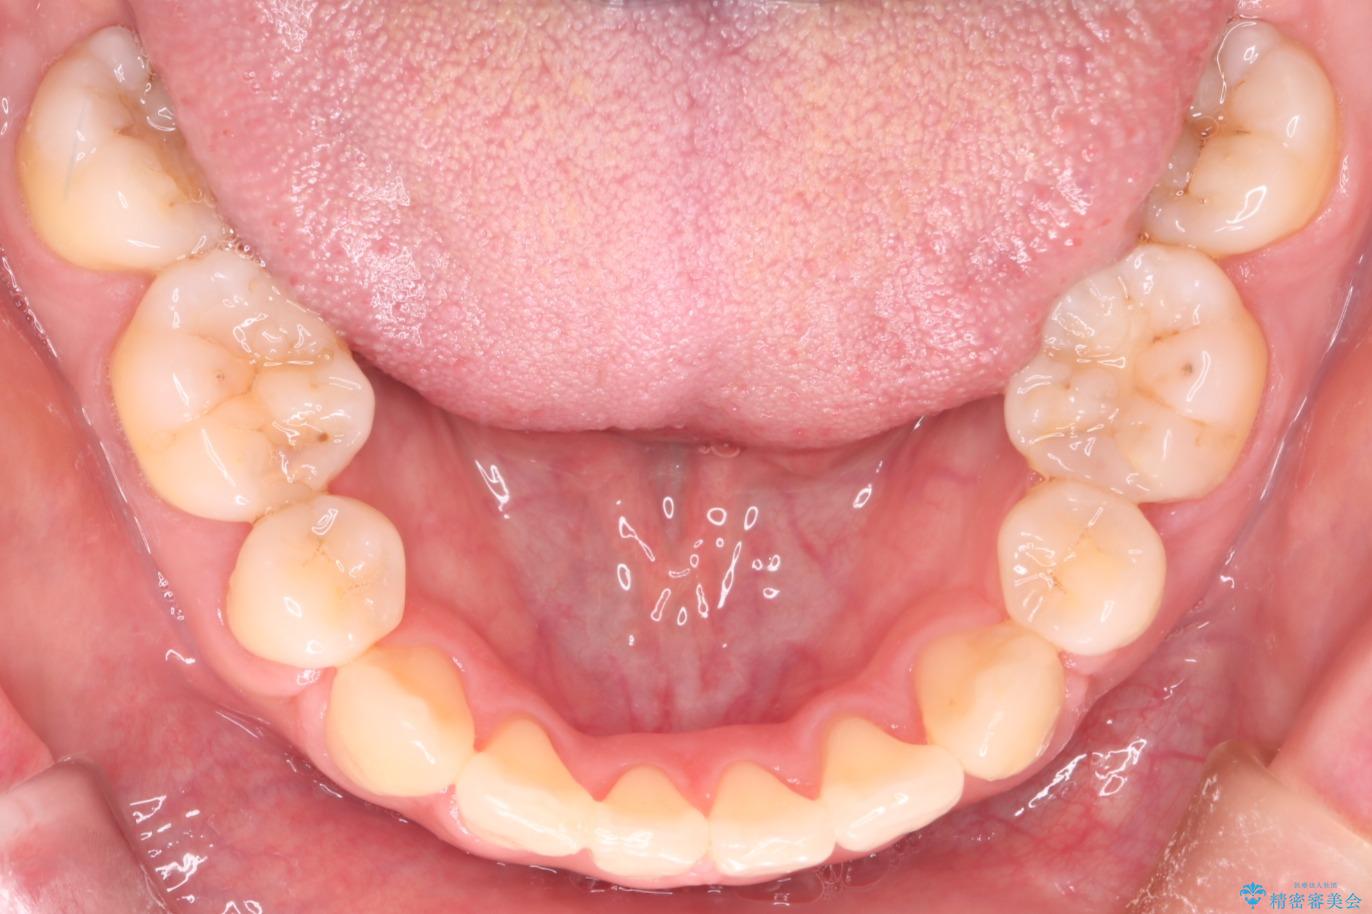

上の前歯のデコボコを主訴にご来院された患者様です。

重度の叢生が認められたため、上下左右4番目の歯を抜歯しワイヤー矯正治療を行いました。

前歯のデコボコが改善され、噛みあわせも綺麗になりました。